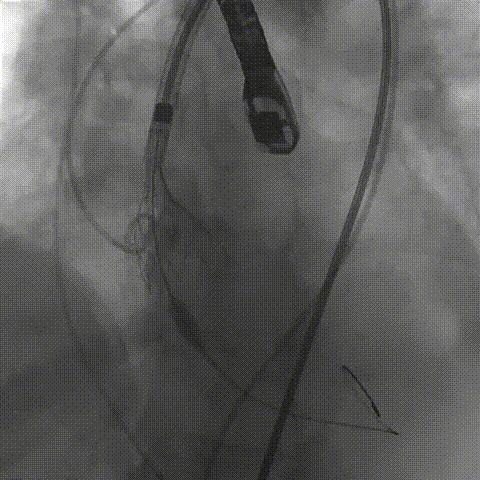

最后造影

术后血流动力学

瓣膜工作状态良好,极微量瓣周漏,血流动力学有效改善